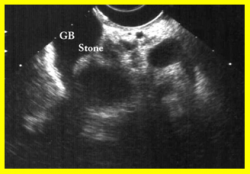

- בדיקת אולטרה-סאונד של כיס המרה (תצלום 1.8).

בדיקת האולטרה-סאונד היא מכשיר עזר חשוב באבחון הלוקים באבנים בכיס המרה, בצהבת או במצבים דלקתיים חריפים. אמינות הבדיקה היא גבוהה - 95%. בבדיקה זו מודגמות האבנים בכיס המרה כנקודות בהירות שמאחוריהן "צל אקוסטי" (Acoustic shadow) - אזור בלא החזרת קול (האבן חוסמת את הקול) (תצלום 1.8). אם הנבדק משנה תנוחה, האבן זזה, והדבר מודגם בבדיקה. אבנים בדרכי המרה ניתנות להדגמה ב- 20% מהמקרים. דרכי מרה מורחבות אפשר להדגים בלוקים בחסימה בדרכי המרה. בחולים אלה ההרחבה יכולה להיות של דרכי המרה החוץ ו\או התוך-כבדיות. (תצלום 2.8 ו- 3.8). נוזל סביב כיס המרה ודופן מעובה של כיס המרה מעידים על דלקת של כיס המרה (תצלום 4.8). אפשר לבצע בדיקת אולטרה-סאונד של דרכי המרה בזמן הניתוח ולאתר אבנים בדרכי המרה.